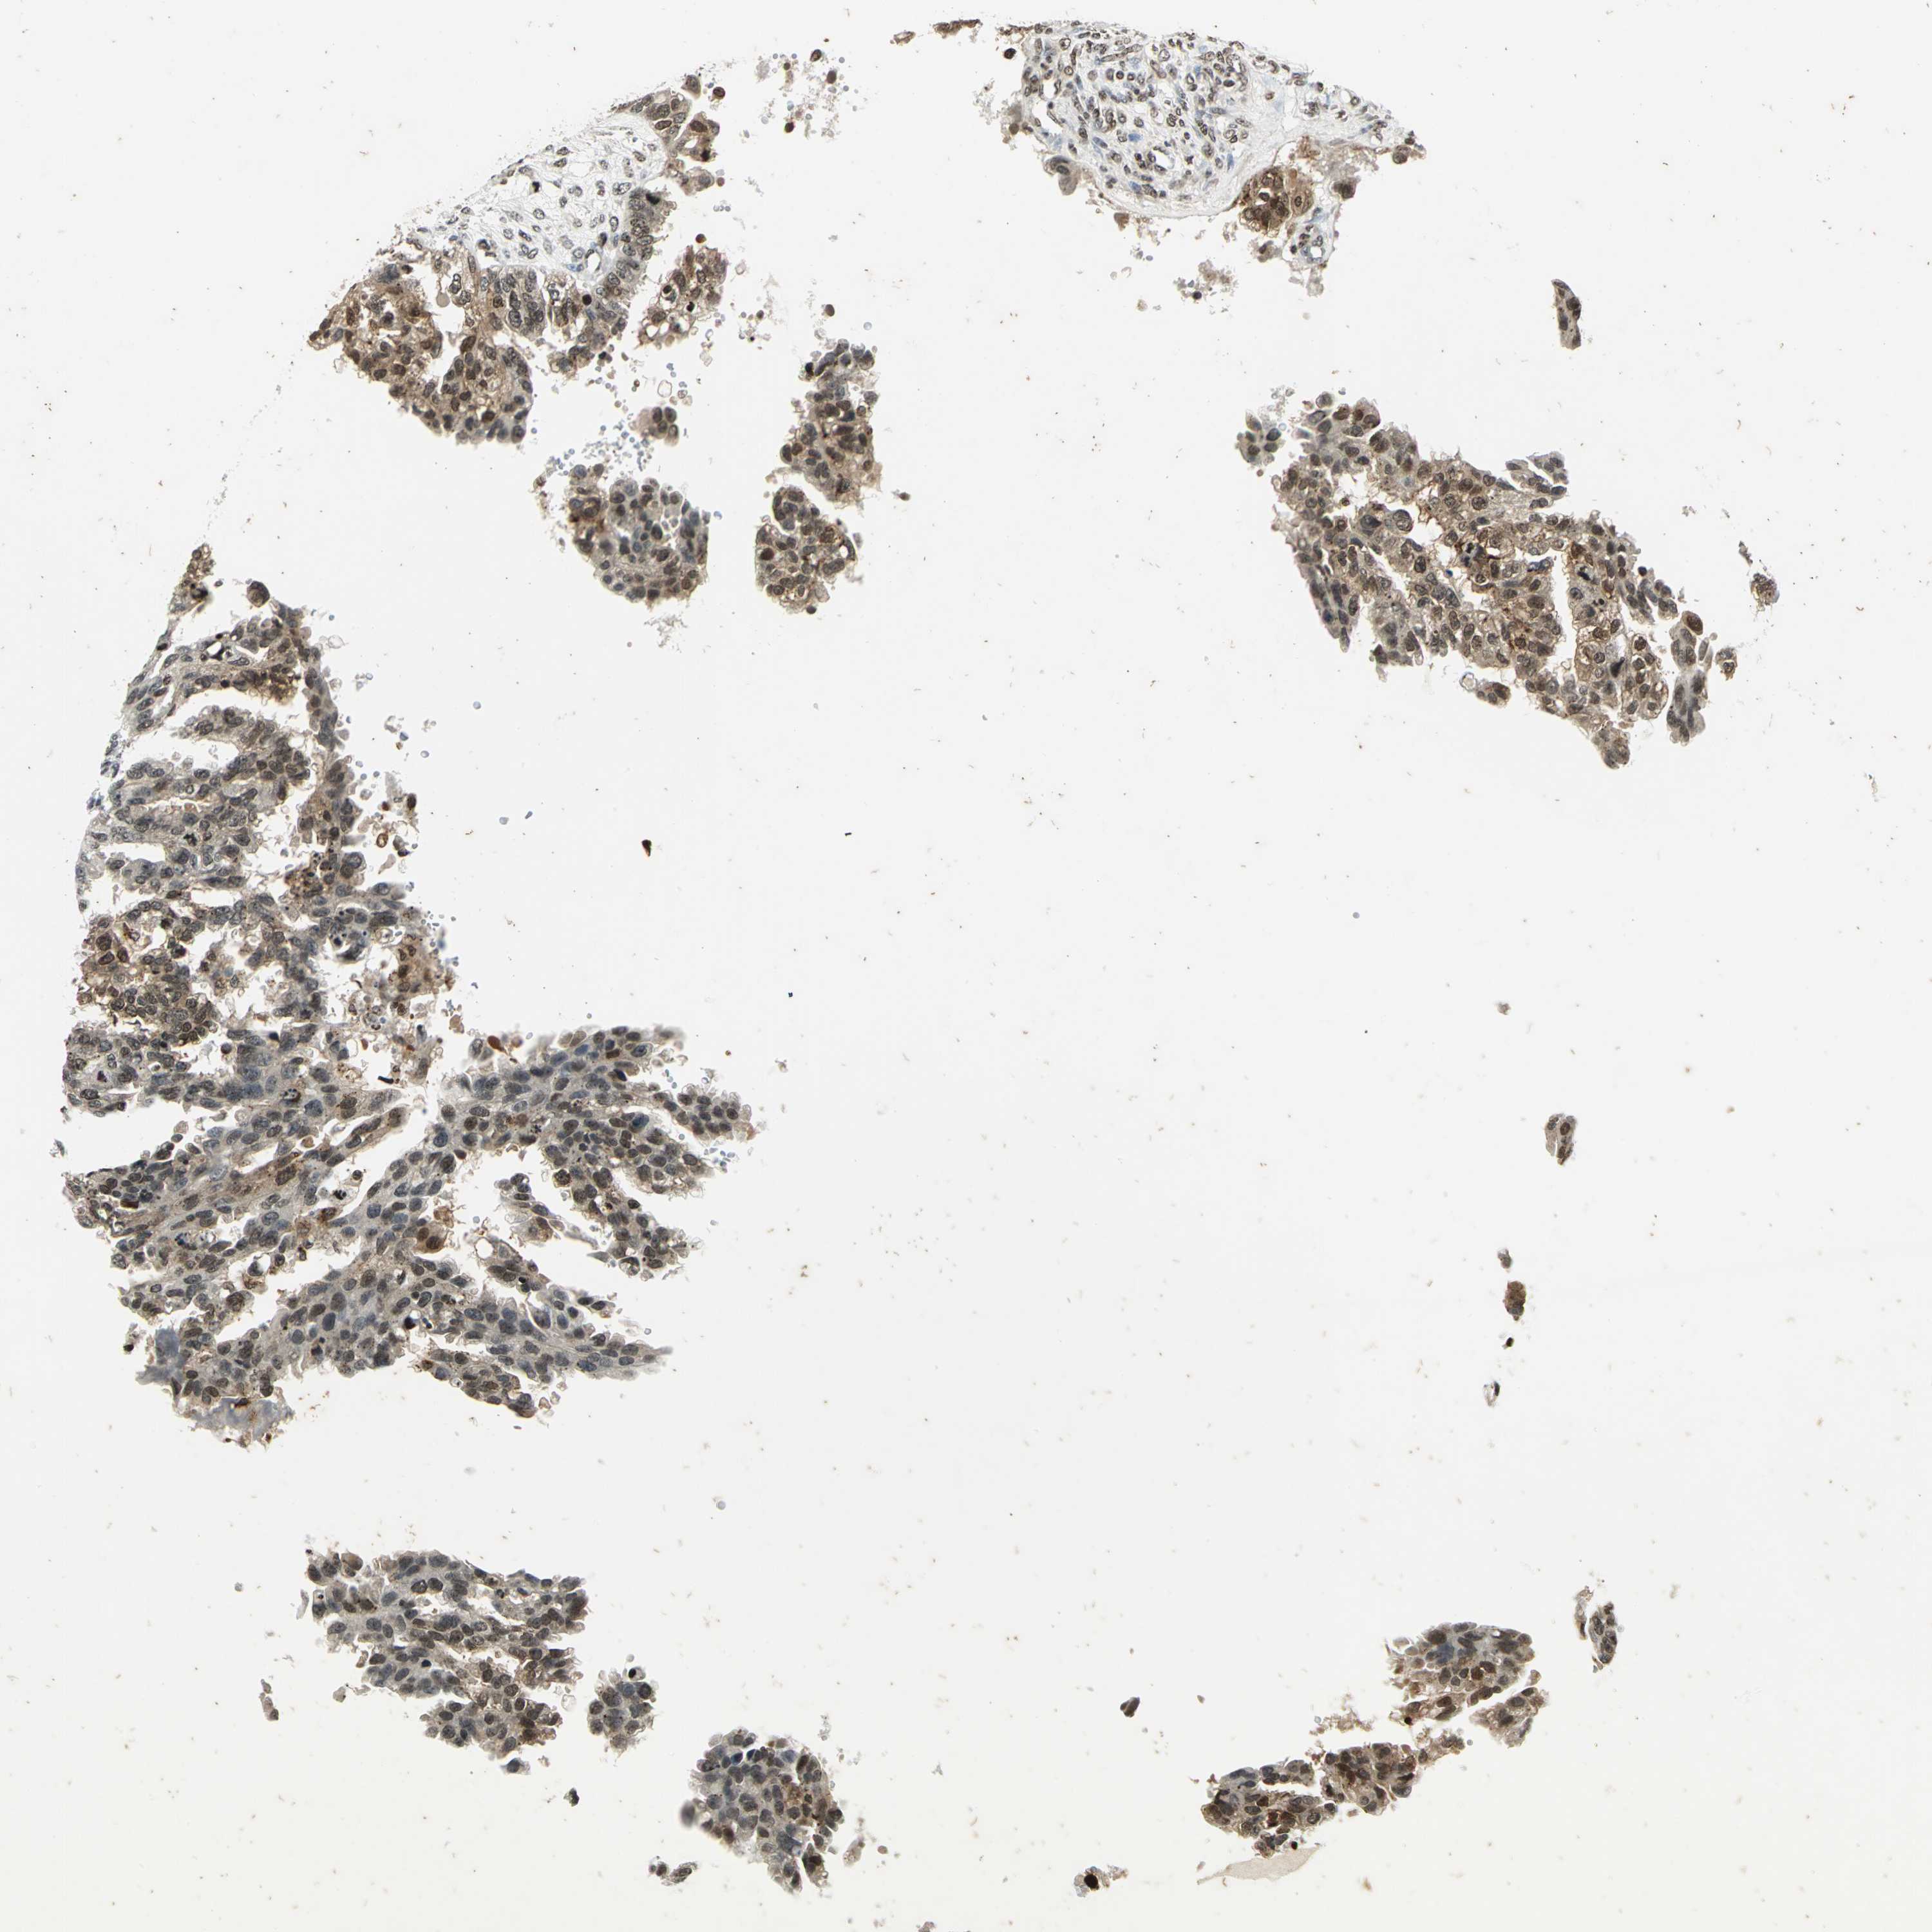

OVARIAN CANCER - Protein expressioni

A mouse-over function shows sample information and annotation data. Click on an image to view it in a full screen mode. Samples can be filtered based on level of antibody staining by selecting one or several of the following categories: high, medium, low and not detected. The assay and annotation is described here.

Note that samples used for immunohistochemistry by the Human Protein Atlas do not correspond to samples in the TCGA dataset.

Antibody stainingi

Antibody staining in the annotated cell types in the current human tissue is reported as not detected, low, medium, or high, based on conventional immunohistochemistry profiling in selected tissues. This score is based on the combination of the staining intensity and fraction of stained cells.

Each image is clickable and will lead to virtual microscopy that enables deeper exploration of all samples and also displays staining intensity scores, fraction scores and subcellular localization as well as patient and tissue information for each sample.

Antibody HPA003162

Antibody CAB005191

Staining

High

Medium

Low

Not detected

Intensity

Strong

Moderate

Weak

Negative

Quantity

>75%

75%-25%

<25%

None

Location

Nuclear

Cytoplasmic/membranous

Cytoplasmic/membranous,nuclear

Cystadenocarcinoma, mucinous, NOS

Carcinoma, endometroid

Cystadenocarcinoma, serous, NOS

Carcinoma, NOS